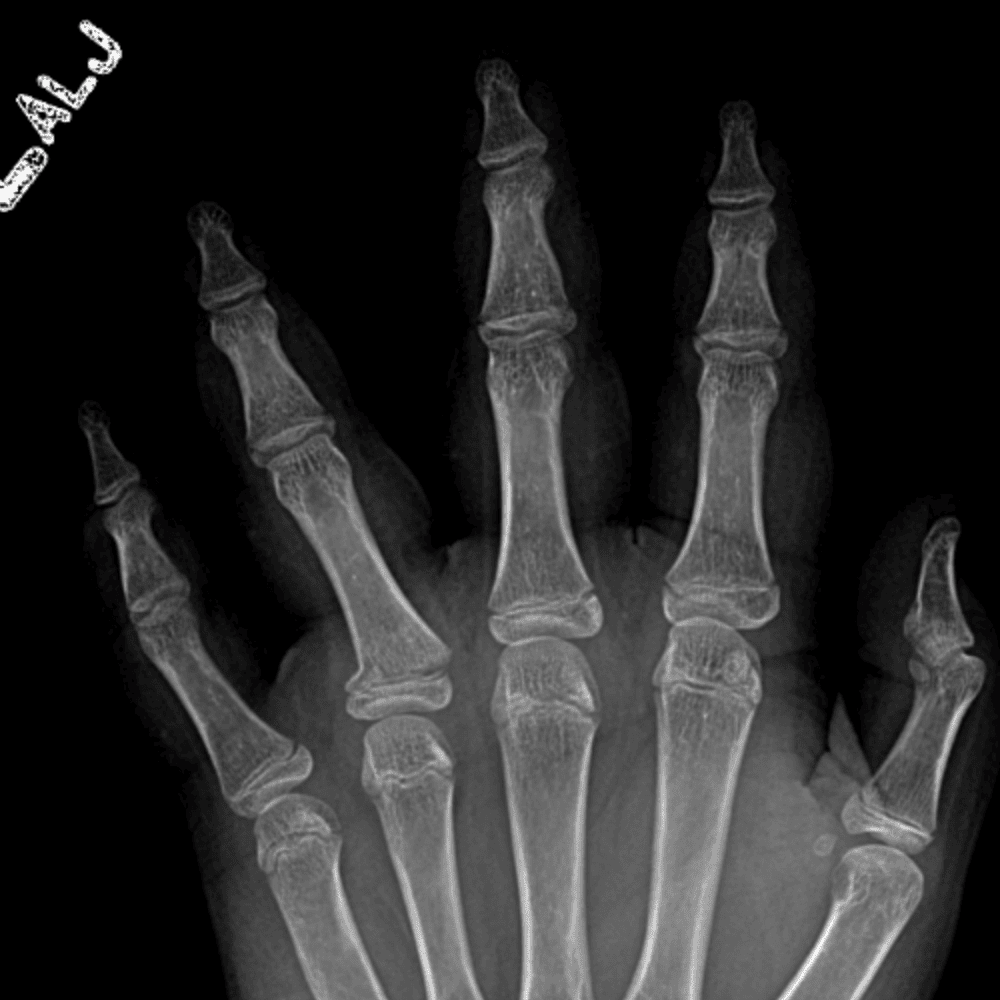

Simulates call by including subtle or difficult cases and some normals.

30 cases